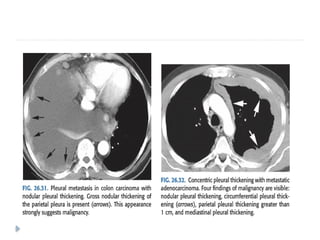

PLEURAL METASTASES

⚫ Adenocarcinomas are known to cause pleural

metastasis than any other histological types of

cancers.

⚫ Common primary sites are from : lung, lymphoma,

and ovary, invasive thymoma

⚫ Pleural effusion is the most common finding on

imaging .